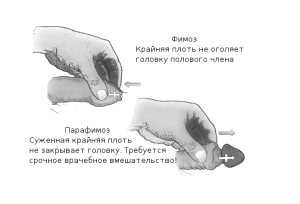

- фимозом,

При набряку і почервоніння голівки, появі хворобливих виразок на ній і крайньої плоті, загальної слабкості та високої температури діагностують гангренозну форму баланопостіта і розвиток фімозу.

- звужується уретра і розвивається фімоз,